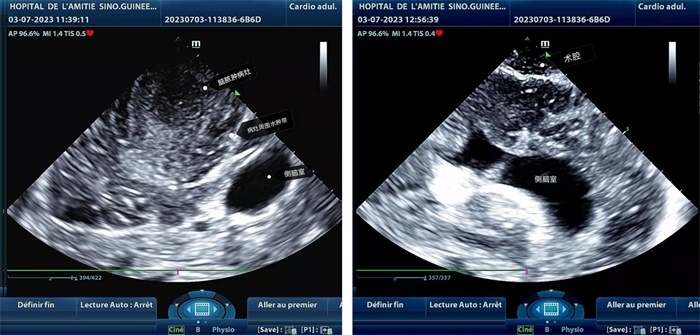

左圖顯示術(shù)中超聲見囊實(shí)性病變,大小約為4x4x3cm,病灶周圍腦組織水腫明顯;右圖為病灶切除后,術(shù)中超聲示術(shù)腔無病變殘留

左圖顯示術(shù)中超聲見囊實(shí)性病變,大小約為4x4x3cm,病灶周圍腦組織水腫明顯;右圖為病灶切除后,術(shù)中超聲示術(shù)腔無病變殘留。中國(guó)第二十九批援幾內(nèi)亞醫(yī)療隊(duì)供圖

手術(shù)中,張國(guó)濱在超聲科顧秀娟的幫助下,運(yùn)用顱腦術(shù)中超聲技術(shù),通過將一次性保護(hù)套的超聲探頭置于腦組織表面,實(shí)時(shí)觀察病變的位置和形態(tài),進(jìn)一步確認(rèn)最佳手術(shù)路徑。術(shù)中超聲顯示,病變位于左額頂葉,大小約為4x4x3cm,邊界清晰,呈囊實(shí)性,周邊腦組織水腫明顯。最終,病灶順利切除,診斷為腦膿腫,并通過超聲檢測(cè)確認(rèn)術(shù)腔無病變殘留、無出血,為患者術(shù)后恢復(fù)提供了良好的保障。